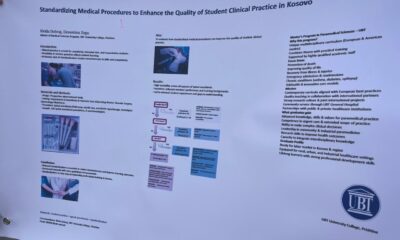

Studentja...